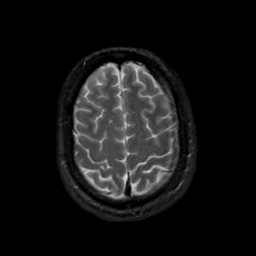

MR Study #19, August 25, 1991 -- Slice #41

[Home][Help][Clinical][Tour 1][Tour 2] Slice 41